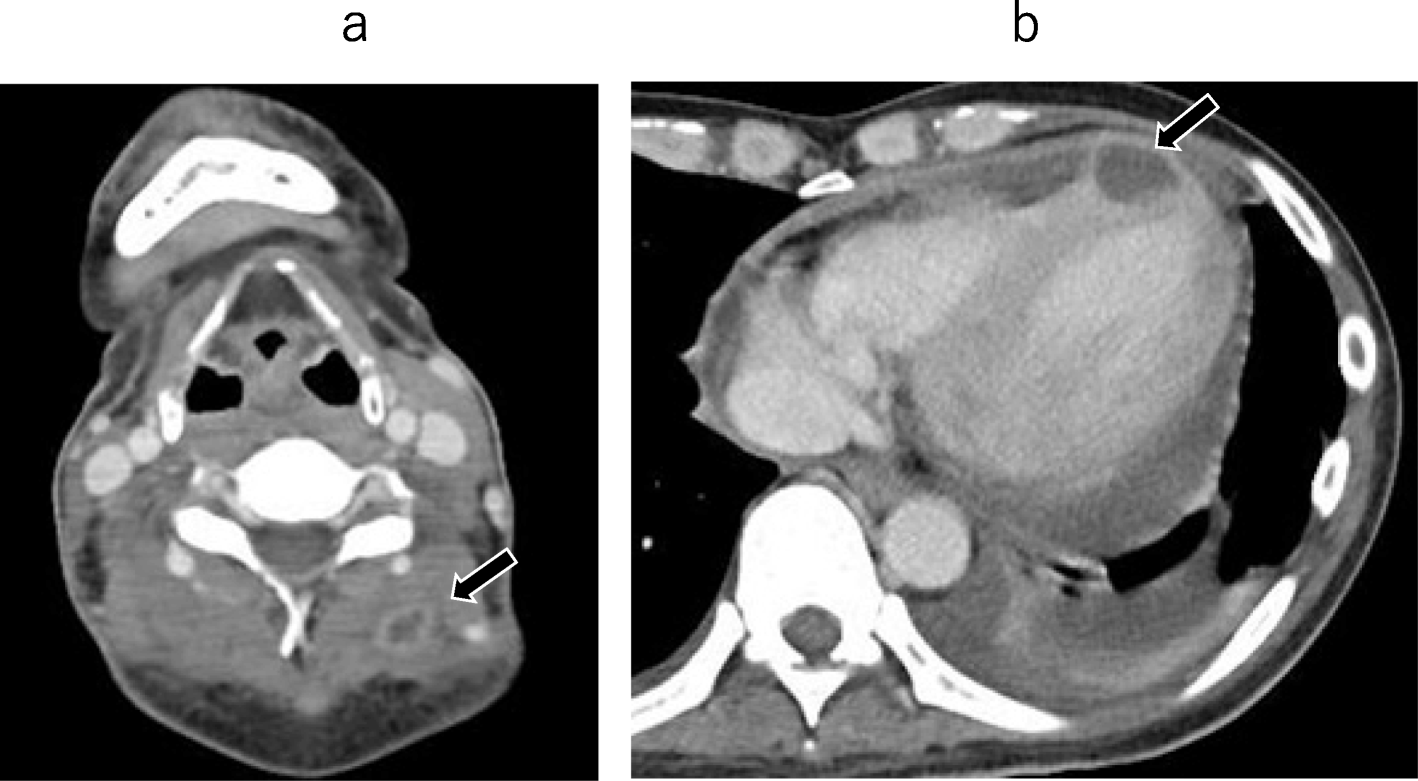

From www.researchgate.net

Case 2 47yearold male patient with primary mural endocarditis and no What Is Mural Endocarditis Infective endocarditis is infection of the endocardium, usually with bacteria (commonly, streptococci or staphylococci) or fungi. Endocarditis is a term that refers to inflammation of the endocardium, the thin inner membrane that covers the heart and heart valves. Infective endocarditis (ie) is an infection involving the endocardial surface of the heart, including the valvular structures, the. Infective endocarditis is defined. What Is Mural Endocarditis.

Case 1 67yearold male patient with primary mural endocarditis and a What Is Mural Endocarditis Infective endocarditis is defined as a disease of the endocardial surface of the heart, with infection primarily involving the cardiac valves (native or. Endocarditis is a term that refers to inflammation of the endocardium, the thin inner membrane that covers the heart and heart valves. Infective endocarditis is infection of the endocardium, usually with bacteria (commonly, streptococci or staphylococci) or. What Is Mural Endocarditis.